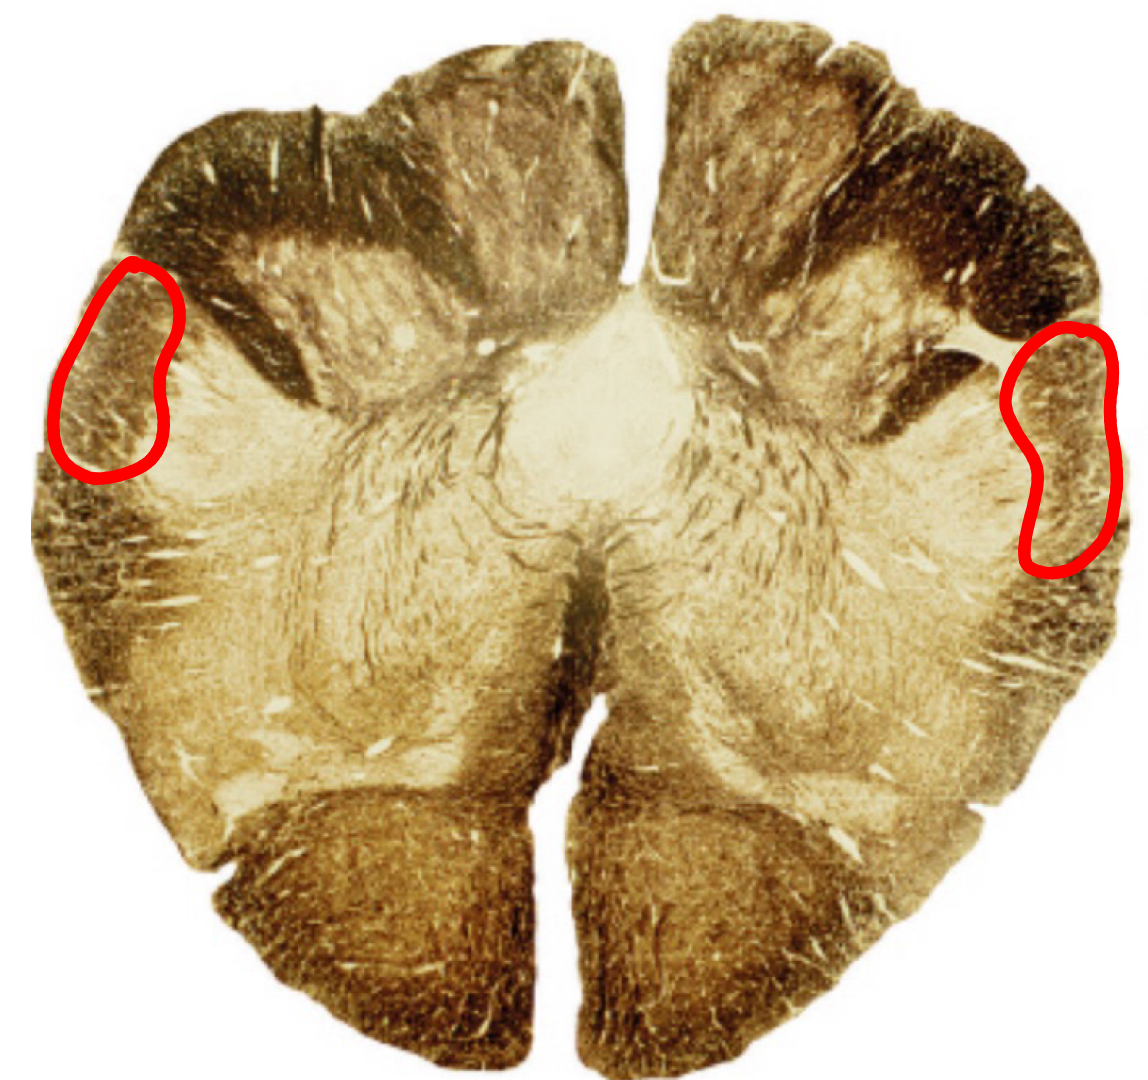

gracile tract caudal medulla II

gracile nucleus caudal medulla II

cuneate tract caudal medulla II

cuneate nucleus caudal medulla II